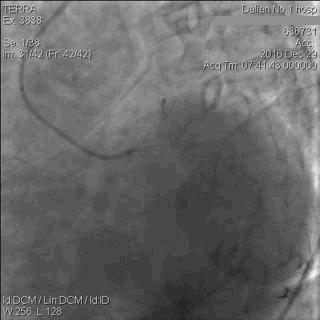

激烈的讨论过后,病例介绍继续。王少鹏教授揭晓,患者在LCx的OM支置入EXCEL 2.5*24 mm支架1枚,在LCx远段行球囊扩张,如图6。

图6 患者进行PCI